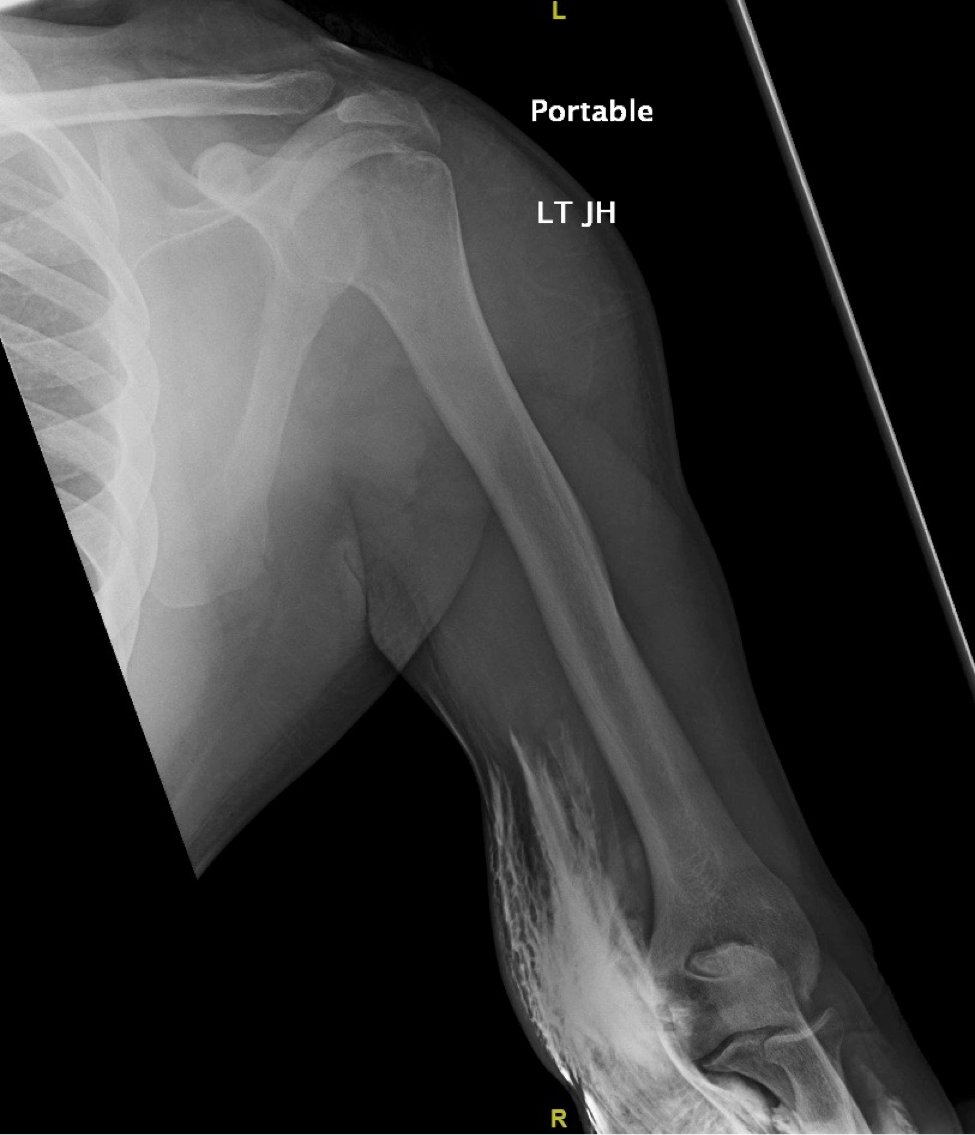

Significant findings:

The two radiographs demonstrate extravasation of radiopaque iodinated contrast in the lower left upper extremity with most seen in the left antecubital fossa and left proximal forearm. Extravasation is seen in the subcutaneous and subfascial tissue.